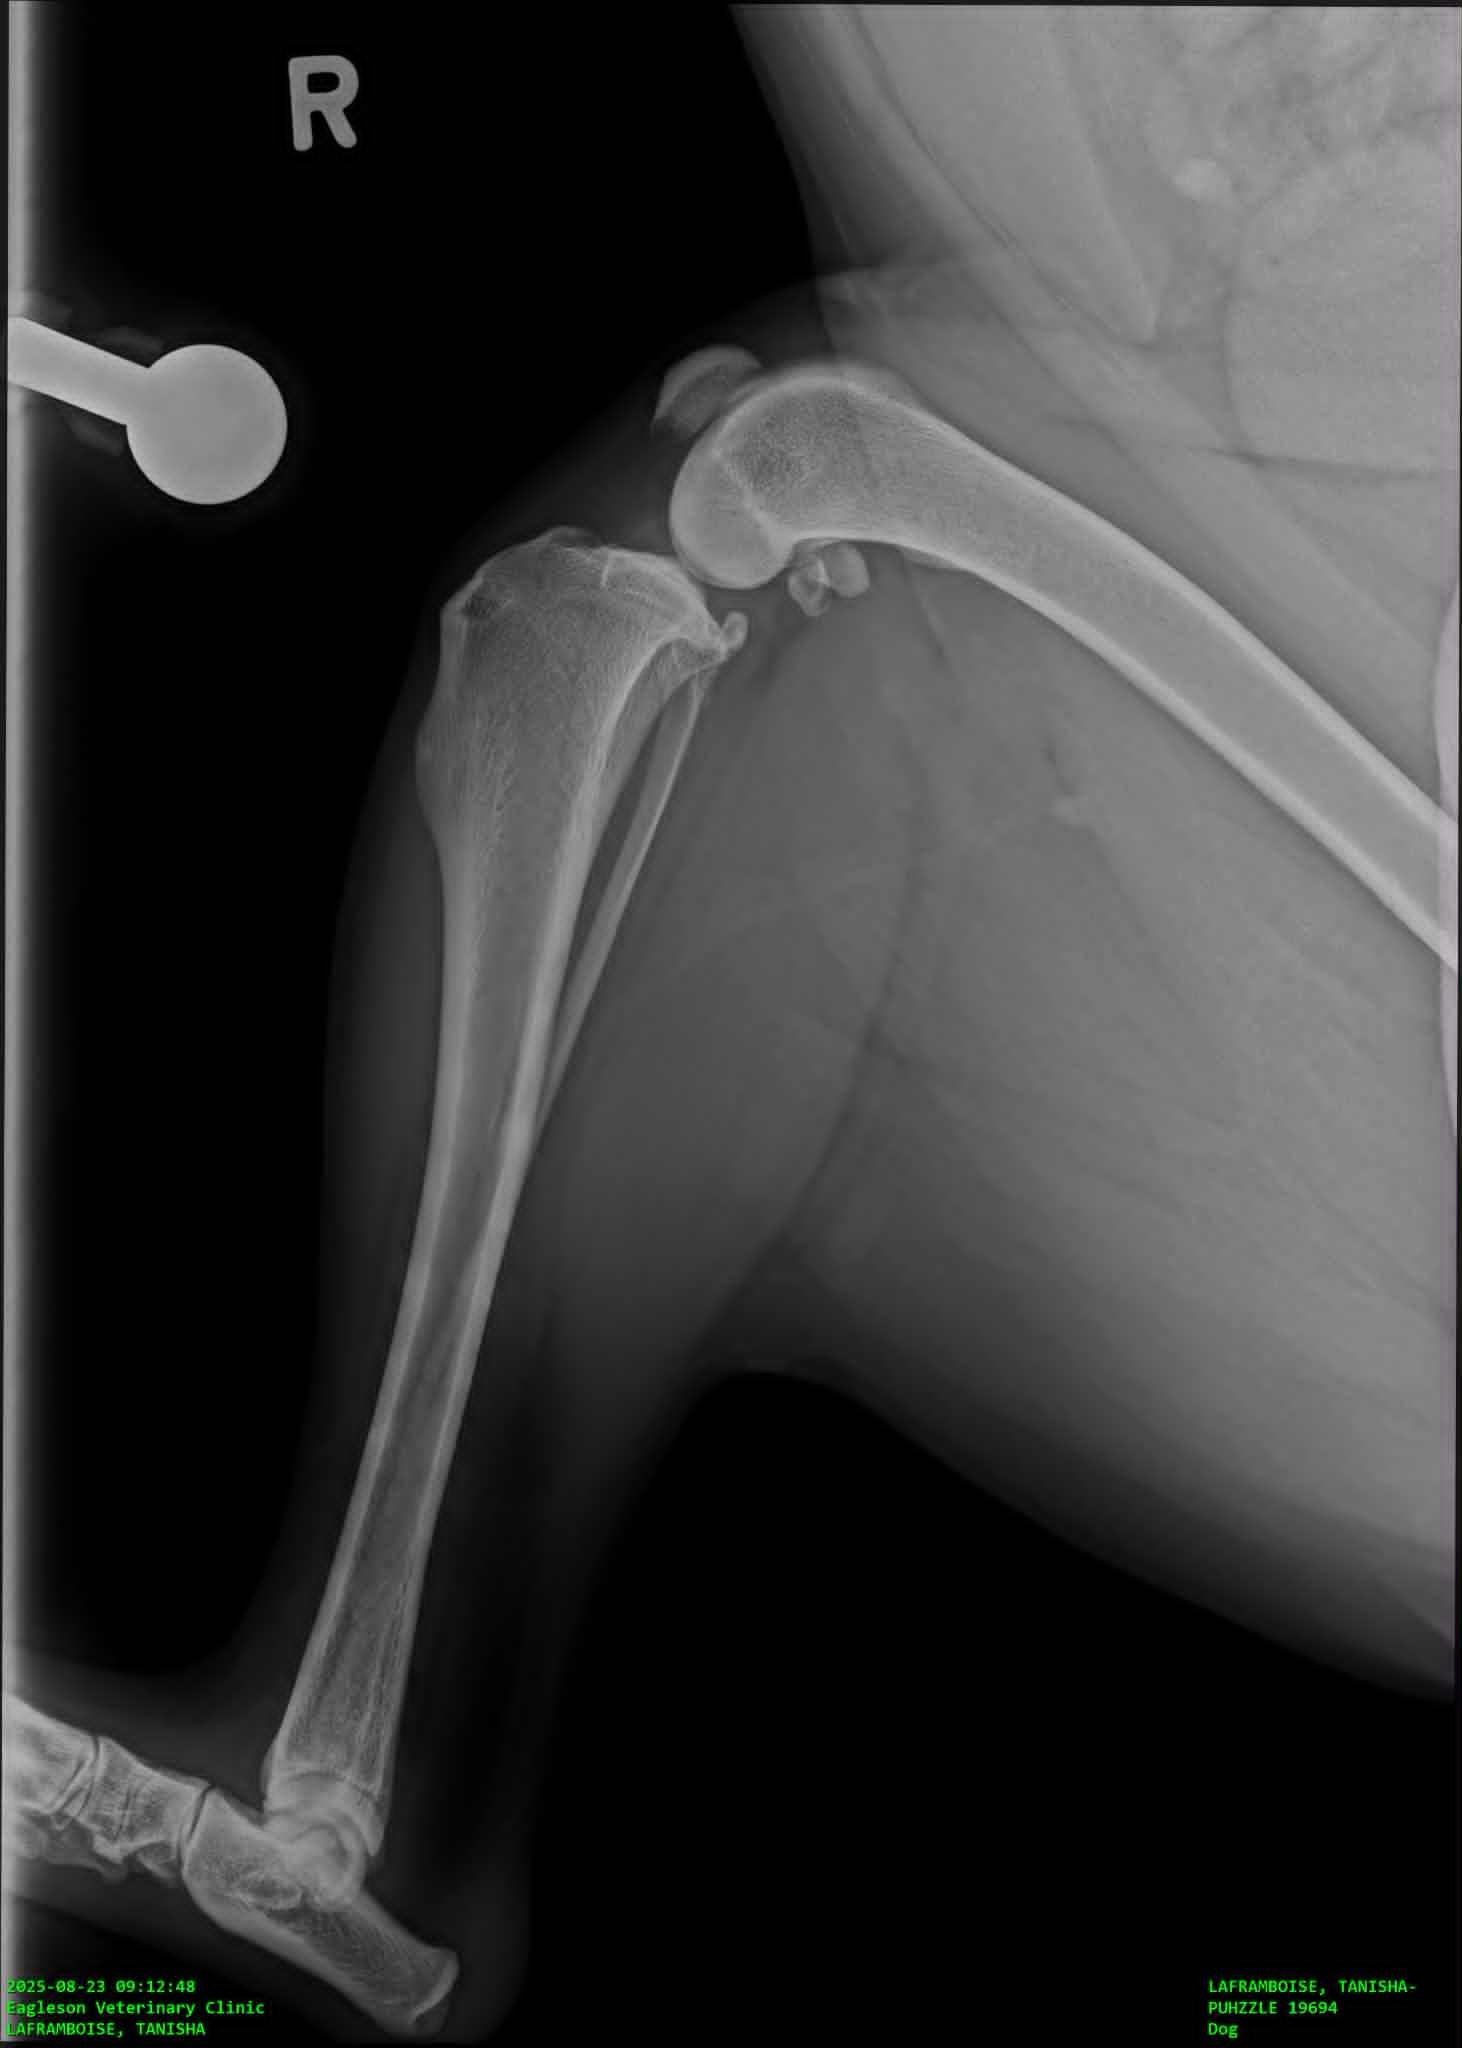

Hello my name is Zach and my wife Tanisha and I are desperately trying anything we can to raise the funds for our dog-ters TPLO surgery. After we had arrived home in the evening my wife noticed she was limping on her walk. We crate rested her for the night and woke up early to see if she would still be limping in the morning. When she was we immediately took her to emergency at our regular vet who did x-rays and actually diagnosed Puhzzle with Bi-lateral hip dysplasia and told us she would need hip surgery. We started some pain management and got a referal to an Orthopedic vet near us to start discussing options. During our consultation with our surgeon he mentioned feeling a little concerned about one of her x-rays and the consultation quickly turned into an exam. He explained to us that yes Puhzzle has Bi-lateral hip dysplasia, but as she's 4 and has had no issues running, jumping, or being a dog that he suspected her hips aren't her current issue. He did an exam on her legs and found she has a partially torn ACL that will require surgery to fix, luckily he mentioned that once they get the TPLO surgery they do not need another on that particular knee and she'll gain 98-99% functionality but the other ACL is high risk for injury within 6-12 months because this injury is genetic, being a structural flaw of how her liagaments rub on the bone while moving. My wife and I are saving everything we can and have her surgery currently scheduled for November 20th, because she needs the surgery sooner than later, to avoid further injuring herself, and any donation towards her surgery would mean so much to us.